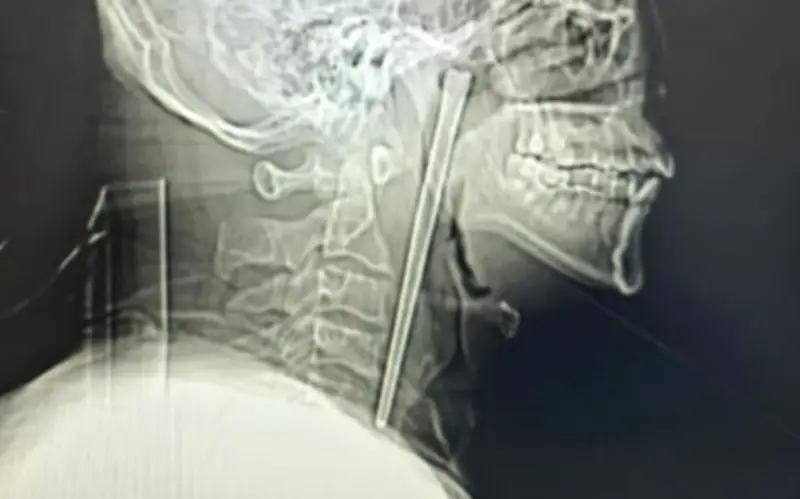

Một trường hợp y tế hy hữu vừa xảy ra tại Đại Liên, Trung Quốc, khi một người đàn ông 46 tuổi được đưa vào bệnh viện vì cơn đau họng dữ dội. Các bác sĩ đã vô cùng kinh ngạc khi phát hiện một chiếc đũa kim loại dài 12 cm bị mắc kẹt trong cổ họng của ông suốt 8 năm qua.

Nhận thấy có điều gì đó không ổn, Wang vội vã đến bệnh viện. Các bác sĩ phát hiện chiếc đũa kim loại bị mắc kẹt ở phía sau cổ họng của ông, với khoảng 3 cm phần đũa nhô ra ở phía trên. May mắn thay, nó không gây ra bất kỳ chảy máu hay loét nào có thể nhìn thấy ở cổ họng.